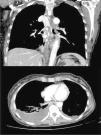

A 60-year-old woman, former smoker, receiving chemotherapy for a diagnosis of ovarian adenocarcinoma, presented with sudden dyspnea, heaviness in the upper limbs, and syncope. Physical examination revealed blood pressure 110/60 mmHg, heart rate 110 bpm, oxygen saturation 95%, erythema and facial edema, and no signs of collateral circulation or lymphadenopathies. On laboratory tests, hemoglobin was only 8.6 g/dl. Chest CT-angiogram showed extensive thromboses in the azygos and hemiazygos veins, with no signs of PE or VCS (Fig. 1). No findings of interest were observed on lower limb ultrasound or echocardiogram. Thrombophilia tests, including antiphospholipid antibodies, were negative. The patient was given weight-adjusted tinzaparin treatment and anticoagulation continued until the end of chemotherapy (9 months), with complete resolution of her respiratory symptoms and no evidence of complications. Repermeabilization of the AVT was observed in the follow-up CT.

Chest CT-angiogram is the test of choice for the diagnosis of AVT, while a CT-venography should be considered if VCS is suspected. In thrombosed AVAs, the use of dynamic multidetector CT with ECG to assess myocardial damage has been proposed.5